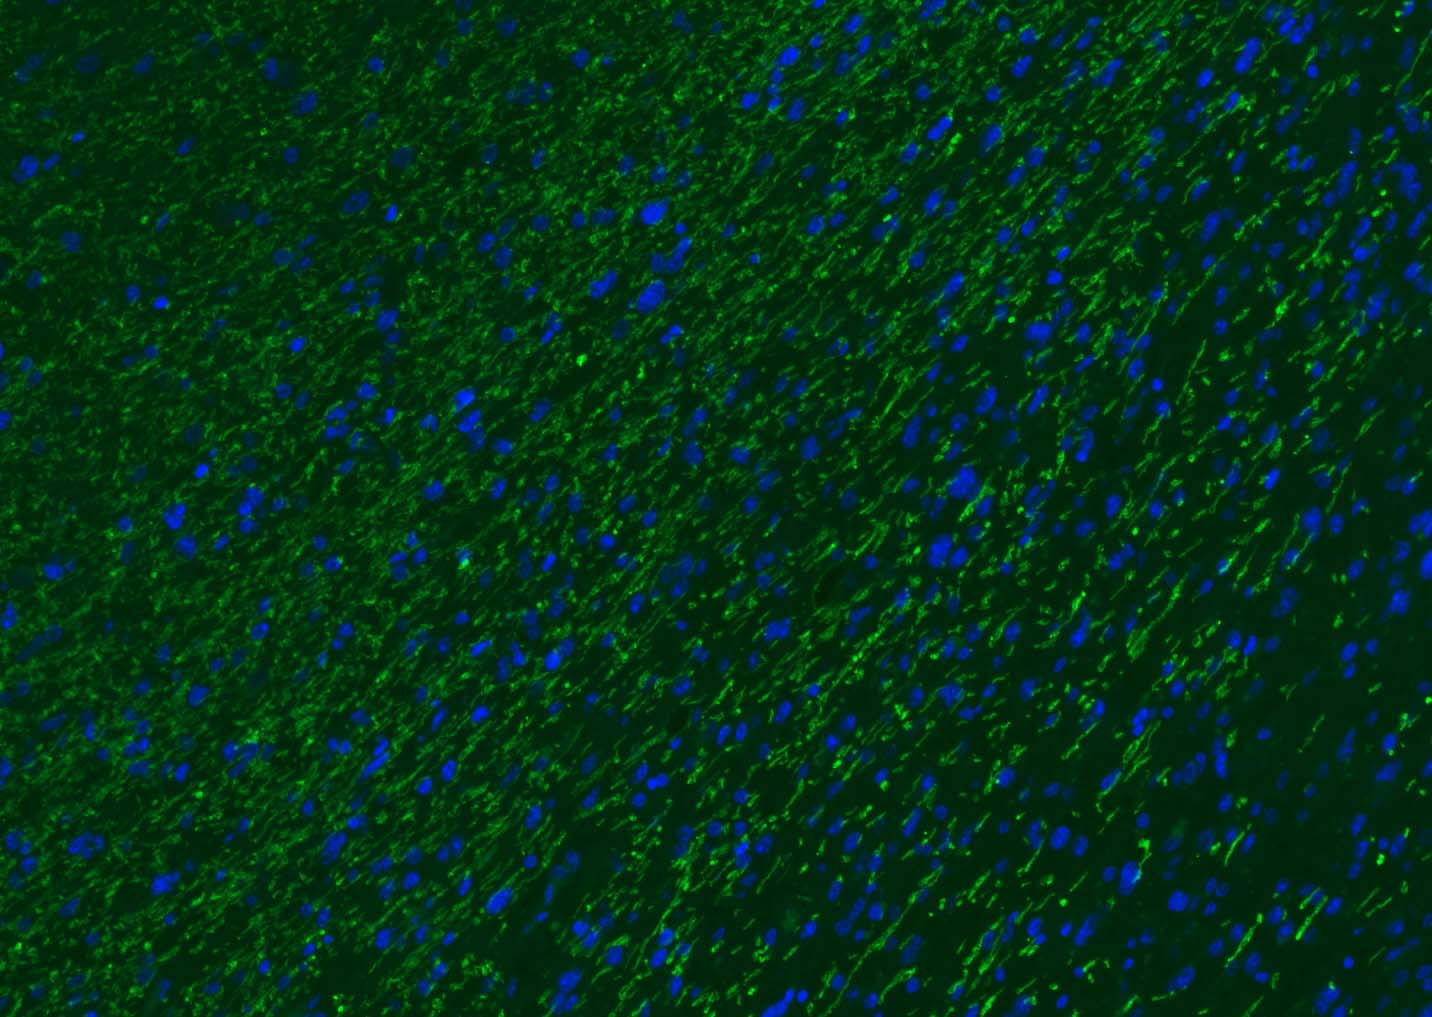

| 背景资料 | Oligodendrocyte Marker The classic group of Myelin basic protein (MBP) isoforms (isoforms 4 to 14) are with PLP the most abundant protein components of the myelin membrane in the CNS. They have a role in both its formation and stabilization. The smaller isoforms might have an important role in remyelination of denuded axons in multiple sclerosis. The non classic group of MBP isoforms (isoforms 1 to 3/Golli MBPs) may preferentially have a role in the early developing brain long before myelination, maybe as components of transcriptional complexes, and may also be involved in signaling pathways in T cells and neural cells. Differential splicing events combined to optional posttranslational modifications give a wide spectrum of isomers, each of them having maybe a specialized function. |

| {IF} | {1:500-2000} |

[IF={{ 7.59 }}] {Yuanxin Zhai. et al. High-efficiency Brain-targeted Intranasal Delivery of BDNF Mediated by Engineered Exosomes to Promote Remyelination. BIOMATER SCI-UK. 2022 Aug;:} {IF} {Mouse}

[IF={{ 7.4 }}] {Ruoyan Xue. et al. Mesenchymal Stem Cell-Derived Exosomes Promote Recovery of The Facial Nerve Injury through Regulating Macrophage M1 and M2 Polarization by Targeting the P38 MAPK/NF-Κb Pathway. AGING DIS. 2024 Apr 1; 15(2): 851–868} {IF} {Rat}